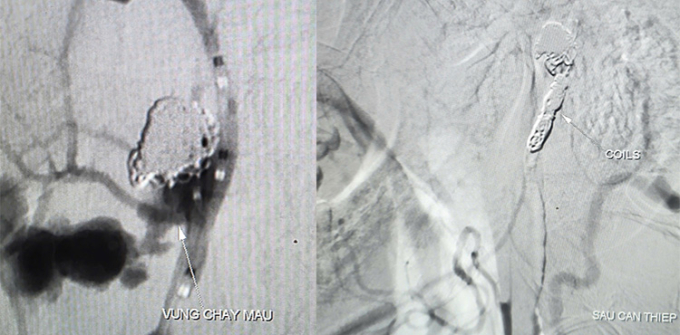

Kết quả CT Scan ghi nhận tổn thương vùng dạng khối choán chỗ khoang niêm mạc hầu của bệnh nhân, xâm lấn vào động mạch cảnh trong, ổ giả phình động mạch cảnh trong đoạn dưới nền sọ. Bác sĩ Trần Công Khánh, Phó Trưởng khoa Chẩn đoán hình ảnh cùng ê kíp chụp và can thiệp cầm máu dưới mạch số hóa xóa nền (DSA) cho bệnh nhân, ghi nhận ổ giả phình động mạch cảnh ở cổ kích thước 4,2 x 4,8 mm, cổ túi phình rộng đang chảy máu.

Êkíp dùng bóng chẹn dòng chảy kiểm soát lượng máu chảy ra, luồn ống thông siêu nhỏ đến vị trí túi phình thả 9 vòng xoắn kim loại (coils) để làm tắc hoàn toàn ổ giả phình và động mạch cảnh, kiểm soát triệt để nguồn chảy máu. Quá trình can thiệp trong 90 phút, bệnh nhân được truyền 6 đơn vị máu, hiện không yếu liệt chi, sức khỏe phục hồi.

Hình ảnh ổ giả phình động mạch cảnh trong phải đoạn cổ bệnh nhân trước và sau can thiệp. Ảnh: Thanh Phong